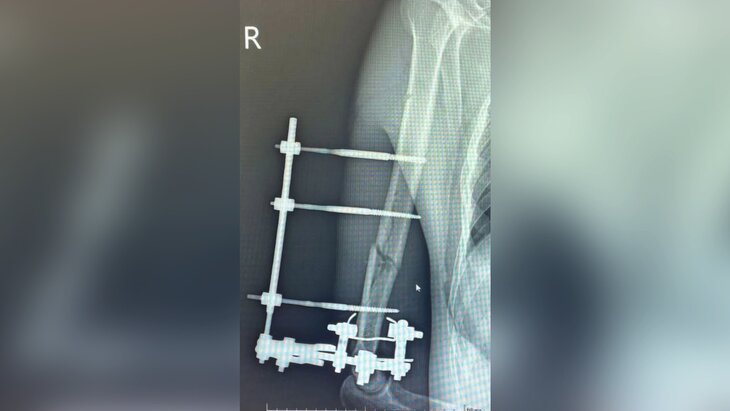

Врачи Истринской больницы спасли 29-летнему мотоциклисту руку, которая почти была оторвана после ДТП с автомобилем. Об этом подмосковный Минздрав сообщил на сайте.

Заведующий травматологическим отделением больницы Роберт Миллер рассказал, что, когда пострадавший мужчина поступил в стационар, его рука держалась только на мягких тканях. Изначально был риск потери руки, однако ее удалось спасти. Врачи выполнили хирургическую обработку, зафиксировали конечность в правильном положении, а затем провели остеосинтез аппаратом Илизарова.

По данным ведомства, мотоциклист пробыл в отделении полтора месяца. Сейчас пациент выписан домой и находится под наблюдением травматолога.